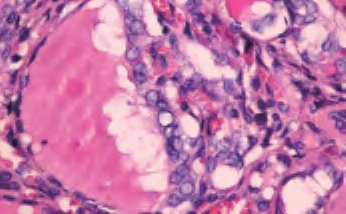

3.镜下 为复杂分支状乳头,含纤维血管轴心,细胞拥挤,核增大,呈卵圆形、沙砾体,表面被以单层柱状上皮,半数以上核呈毛玻璃样,有核沟,核内假包涵体(图3-40至图3-43)。

图3-40 甲状腺乳头状癌

图3-41 甲状腺乳头状癌